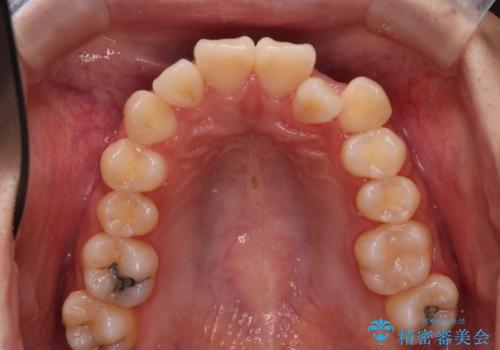

反対咬合を治したい。インビザライン

- 前歯の反対咬合を治したいことを主訴に来院されました。

インビザラインにて臼歯の遠心移動を行いながら、スペースを作り反対咬合を改善することができました。